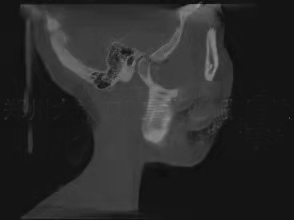

颞下颌关节由关节窝、髁突、关节盘及其周围软组织构成。髁突位于关节窝内,关节盘将髁突与关节窝分割为上下两个间隙,以避免骨性凹陷与髁突直接接触造成损伤。一般来说,髁突在关节窝中的矢状向位置关系更容易受到咬合闭合道及闭口位的影响,从而建立不良的关节结构关系,把关节盘挤出关节窝,造成髁突与关节窝之间的直接接触,损伤髁突。 髁突在关节窝中处于什么样的生理位置才有利于关节的功能运动及咬合,评价标准一直不统一。 近年来,更多的研究结果证实,在关节结构正常的条件下,牙尖交错位时的髁突在矢状向上基本处于居中的位置,即前后间隙甚至包括上间隙基本相等,这可以作为关节结构分析的参考。同时,牙尖交错位时,关节结构及其周围肌群甚至牙周状态均是协调舒适的,下颌运动时所有结构在这个过程中是轻便无障碍的。然而,这些理论均是建立在关节结构没有损伤的前提下,一旦结构发生损伤,比如髁突吸收,很难找到一个可量化的标准,理想的量化标准只能作为参考。 对于损伤后的关节,如何定位和评价其结构是否合理,目前没有相关概念和指标进行描述。理论上认为,颞下颌关节结构正常时,髁突在关节窝中的位置居中;已经损伤的髁突在关节窝中应有一定的修复空间,无论关节盘处于什么样的状态,只要在临床上患者没有任何不适且下颌功能正常,并经过一定时间的观察发现预后良好,就可以定义为关节舒适位。“舒适的”不一定全是形态健康完整的,损伤后的结构在舒服的环境中有可能慢慢修复;在不舒服的环境中,健康无从谈起。截至目前,还没有公认的关于关节结构,尤其是髁突位置和关节盘状态准确的、定论性的统一标准,也没有关于关节功能紊乱患者的治疗评价标准。

对咬合异常患者要进行临床检查、面型分析、影像学检查等,然后对结果进行综合分析。临床面诊是第一位的,不仅可以看到患者静态的一般情况、面部和咬合特征,还可以观察到患者包括肌位、牙位状况在内的咬合运动、语言、呼吸、发音等功能特征。动态观察一定不可忽略。 除此之外,基于功能运动的咬合分析,对关节病患者使用什么仪器和检查方法,要根据具体情况选择。比如,对下颌各种运动形式的各种检查,可以观察到下颌的运动状态及牙齿尖窝接触点的情况,用来分析咬合是否有碍关节结构和功能的敏感点。具体的方法包括观察法、手诊法、咬合纸检查、T-Scan(T-扫描)动态咬合力检查、髁突运动轨迹描记、头影测量、夜磨牙片、牙尖斜度测量、锥形束CT检查、MRI(磁共振)检查等。 需要注意的是,所有的测量方法都有侧重,医生可以根据实际需要选择一种或几种方法。 一般来说,应用单一的方法难以准确地发现问题;几种方法联合应用,相互印证,相互补充,能让医生更加全面地分析是否存在不足或不正确。但是,对于致力于咬合病治疗的专业人士,掌握头影测量、锥形束CT和MRI的检查方法、制取与分析很有必要,这些也是比较基本的技能;否则,很难做出一个完整、系统、科学的治疗方案。